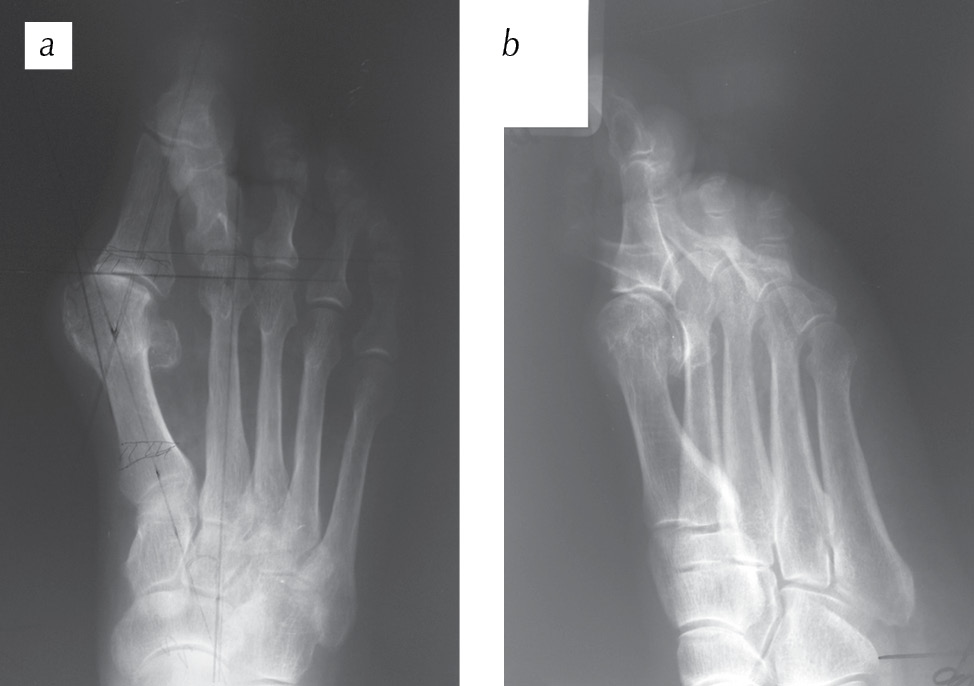

Через 6 нед. после операции спица, фиксирующая II палец правой стопы, и гипсовая иммобилизация удалены, пациентке разрешено ходить с полной нагрузкой на правую нижнюю конечность. Рентгенологический контроль представлен на рис. 6.

Рис. 6. Рентгенограммы переднего отдела правой стопы пациентки Е. через 6 нед. после операции: а — прямая проекция; b — косая (3/4) проекция. Спица, фиксирующая II палец, удалена. Признаки консолидации места остеотомии основания I плюсневой кости с внедренным углеродным наноструктурным имплантатом

Fig. 6. Radiographs of the anterior part of the right foot of patient E. 6 weeks after the operation: а — straight projection; b — oblique (3/4) projection. The pin fixing the second toe has been removed. There are signs of consolidation of the osteotomy site of the first metatarsal bone base with an implanted carbon nanostructured implant

Спустя два года после оперативного лечения функциональные и косметические результаты хорошие, не испытывала дискомфорта при ходьбе и неудобства при ношении обуви (см. рис. 7, 9). Однако при выполнении компьютерной томографии правой стопы в области остеотомии основной фаланги I плюсневой кости прослеживалось наличие углеродного наноструктурного имплантата (рис. 8).

Рис. 7. Рентгенограммы переднего отдела правой стопы пациентки Е. через два года после оперативного лечения: а — прямая проекция; b — косая (3/4) проекция. Консолидация места остеотомии основания I плюсневой кости. Остеоартроз I плюснефалангового сустава

Fig. 7. Radiographs of the anterior part of the right foot of patient E. 2 years after the surgery: а — straight projection, b — oblique (3/4) projection. There is a consolidation of the osteomy place of the first metatarsal bone base. Osteoarthritis of the I metatarsophalangeal joint